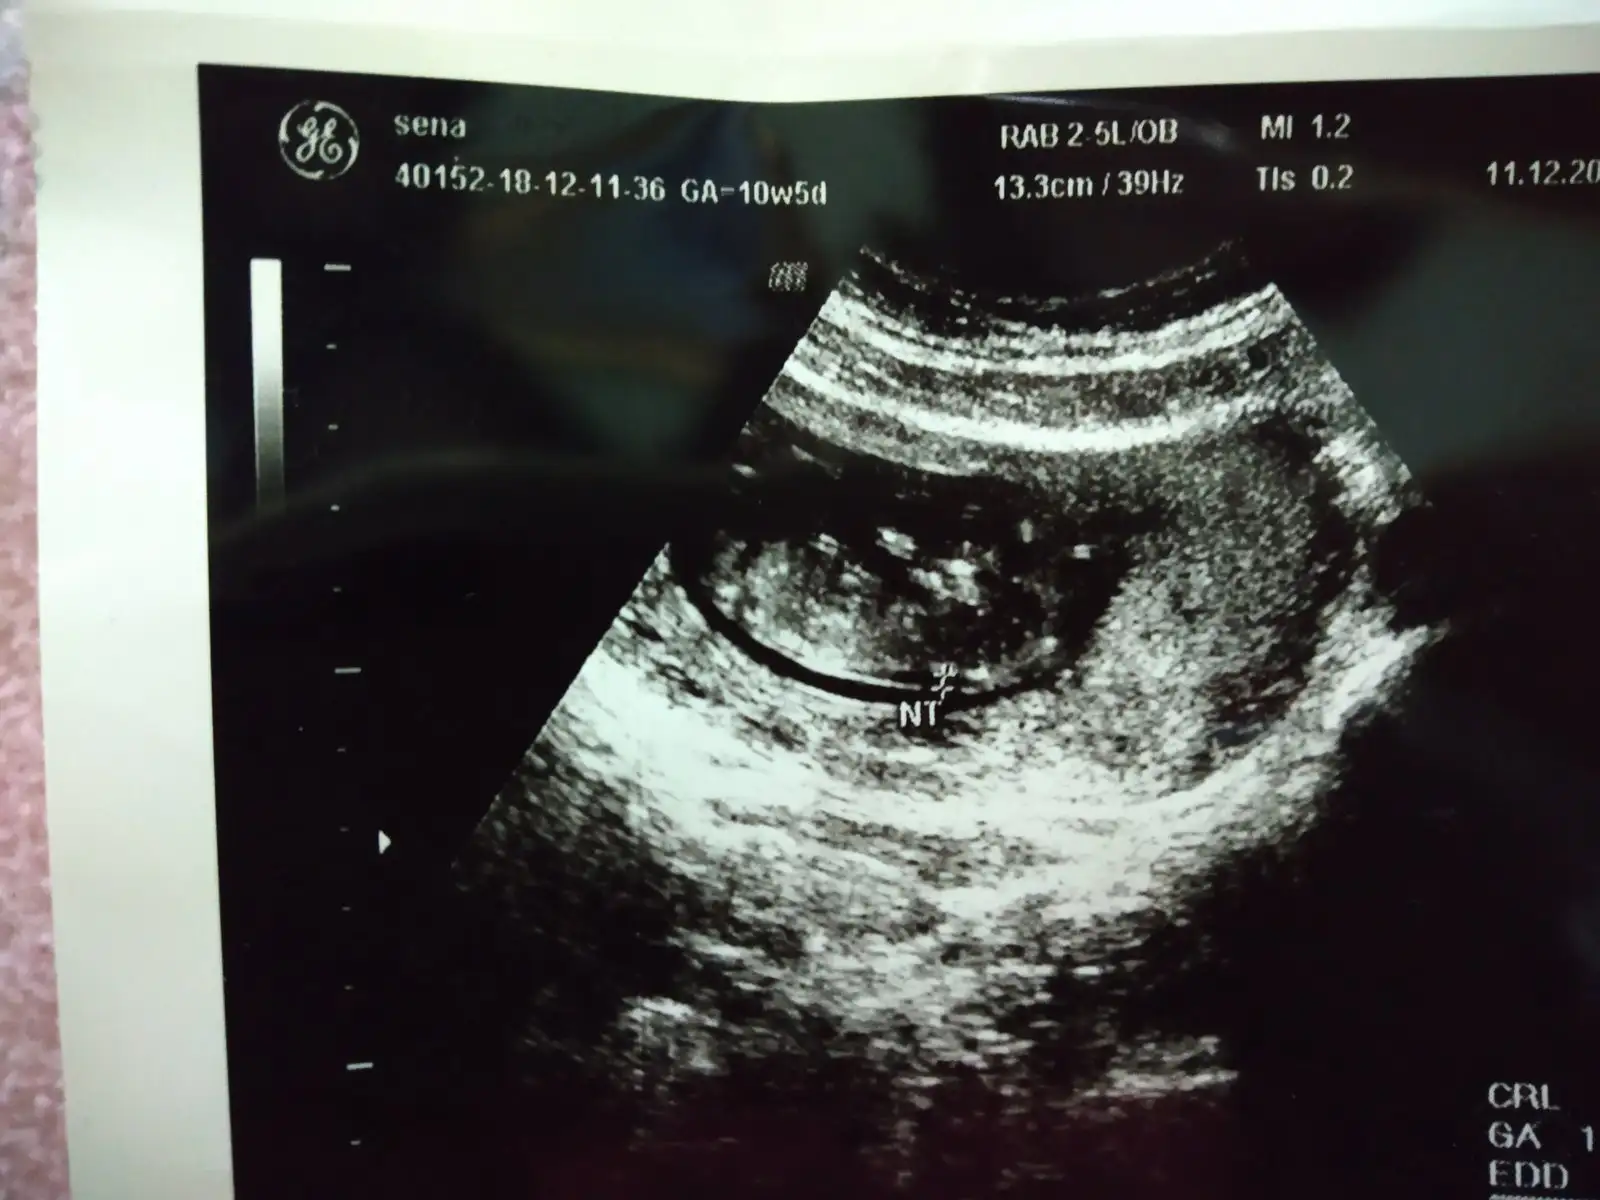

ultrason resminizi gorebilirmiyim merak ettim cnmEşim aha su pipisi diye bağırınca doktor bı kahkaha attı çok yüksek ihtimalle erkek iki hafta sonra net olarak söylerim dedi :)) ense kalınlığına burun kemigine falan da baktirdik :)

ultrason resminizi gorebilirmiyim merak ettim cnm